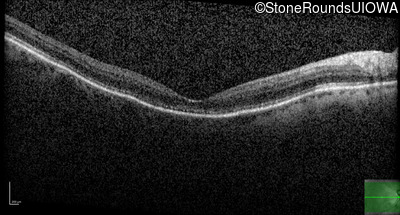

The clinical features favoring the diagnosis of RP1L1-associated occult macular dystrophy include: reduced acuity with a near-normal ophthalmoscopic appearance, a history of normal acuity in childhood; and, a "moth-eaten" appearance of the macular ellipsoid zone on OCT.

Age at visit: 75 years